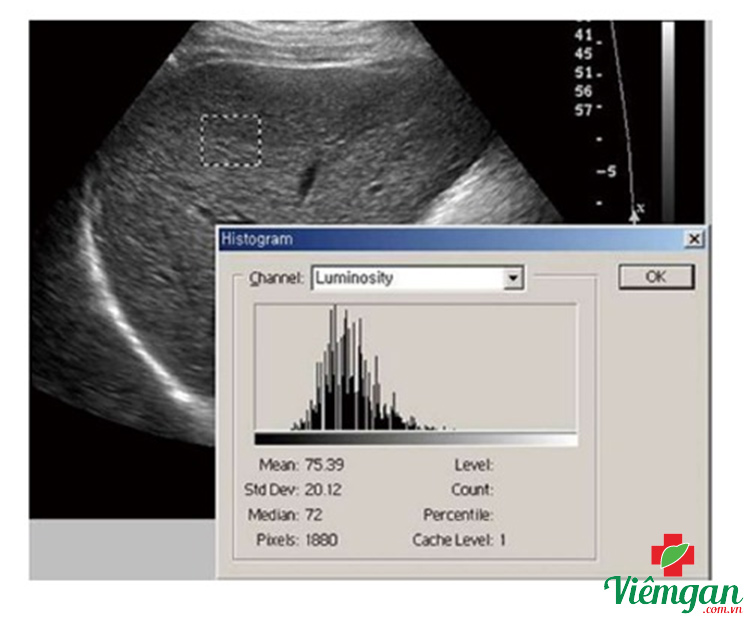

Hình ảnh 2

Phân tích kết cấu tại thùy phải của gan nhờ việc quét liên sườn bằng siêu âm thang màu xám cho thấy nhu mô không đồng nhất, có giá trị lệch chuẩn cao (Diện tích: 1880 pixel, Trung bình: 75,39, SD: 20,12).